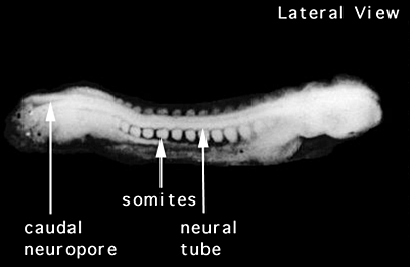

Se forma el tubo neural el cual se convertirá en el sistema nervioso central.

Fusión de las células que dan inicio a la formación de lo que sera la médula espinal.

Formación del tejido que posteriormente se convierte en las vertebras y algunos otros huesos.